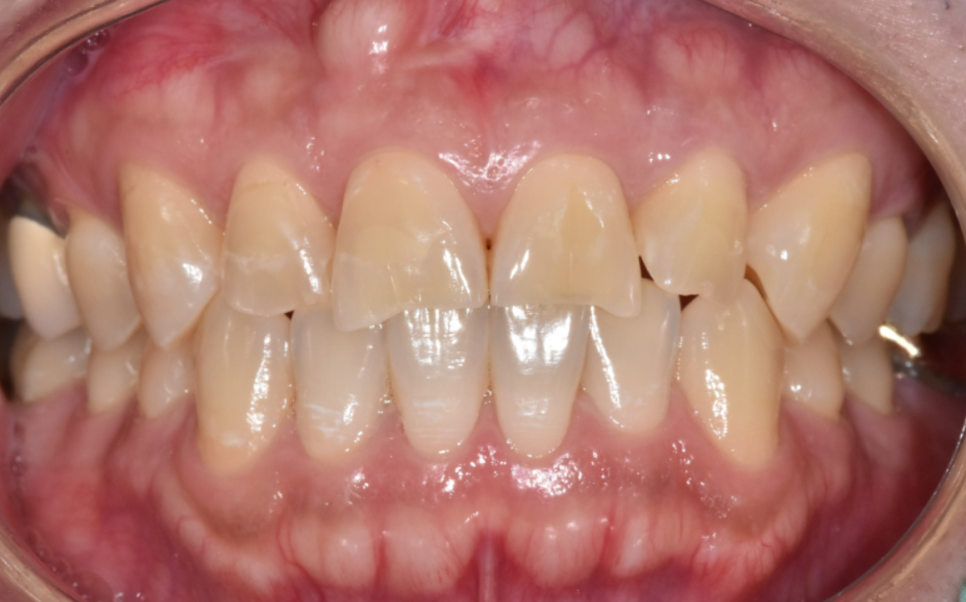

교합을 확인했을 때도

위 앞니가 아래 앞니를 살짝 덮는

정상 범주의 교합이어서,

221208

레진으로 수복하더라도

쉽게 다시 깨질 가능성은 높지 않은 상태였습니다.

그래서 내원한 당일에 레진으로

자연스럽게 앞니 형태를 회복해 드렸습니다.